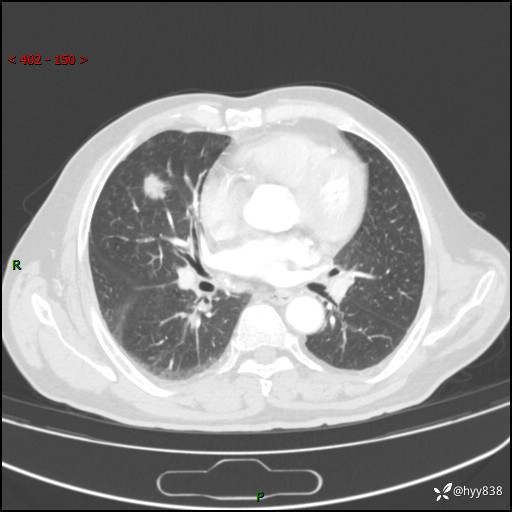

胸部CT复查(2024.7)

CT导向穿刺(靶点---2个结节)